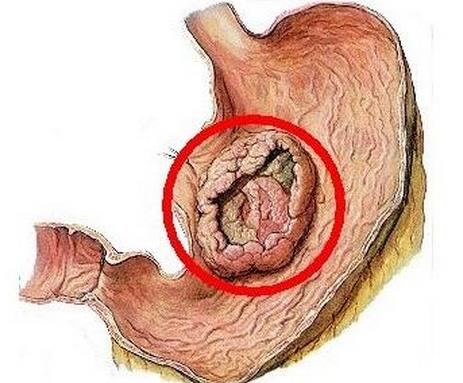

3ĪóĖ╬░®

Ė╬░®╩Ūę╗ĘN╬Ż║”ąįśO┤¾Ą─É║ąį─[┴÷Ż¼ėąę╗Č©Ą─╝ęūÕ╩ĘĪŻĖ╬░®░l▓ĪĄ─įŁę“▒╚▌^Å═ļsŻ¼Ģ■╩▄ĄĮŁhŠ│Īóļ[╦Į║═▓ĪČŠĖą╚ŠĄ─ė░ĒæŻ¼│ŻęŖĄ─░YĀŅ╩ŪĖ╬ģ^╠█═┤ĪóĖ╣├øĪóĘ”┴”ĪóõN╩█Ą╚ĪŻ